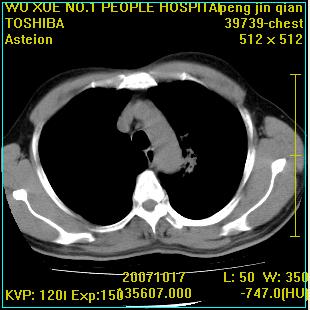

标题: CT10148:男,56岁,咳血。 [打印本页]

标题: CT10148:男,56岁,咳血。

左肺上叶尖段占位性病变,考虑肺癌.癌性空洞,并双肺转移灶及纵隔淋巴结转移

左肺上叶尖后段较大团块影,边缘光滑,内见不规则裂隙样空洞,周围明显见细小结节及渗出,与肺门方向结构紊乱,另:左上叶尖段外侧 舌叶内侧 右上叶尖段及下叶背段均见片状致密影。考虑:继发性肺结核伴空洞形成!

左上肺厚壁空洞影、两肺多发小片样不规则高密度灶。基本上能排除转移瘤。考虑肺结核伴空洞形成。

左上肺后壁空洞,内壁不规则,可见壁结节;左上叶尖段外侧 舌叶内侧 右上叶尖段及下叶背段均见片状致密影。考虑:左肺肺癌并两肺继发性肺结核?

左肺上叶尖后段较大团块影,边缘光滑,内见不规则裂隙样空洞,周围明显见细小结节及渗出,与肺门方向结构紊乱,另:左上叶尖段外侧 舌叶内侧 右上叶尖段及下叶背段均见片状致密影。考虑:继发性肺结核伴空洞形成!建议进一步检查,除外肺癌

右肺下叶背段/左上肺/左下肺结核伴空洞形成

结核 空洞伴两肺播散

浸润型肺结核伴左上肺空洞形成,两肺播散灶